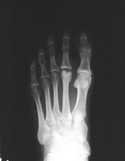

If you see one Freiberg's infraction, you've seen them all, as they say. The radiographic signs are very consistent and typical as seen below.

The radiographic signs of Freiberg's infraction seen here include increased sclerosis, fragmentation and collapse/flattening of the second metatarsal. Other signs specific for this location include widening of the metatarsal head and widening and cortical thickening of the metatarsal shaft.